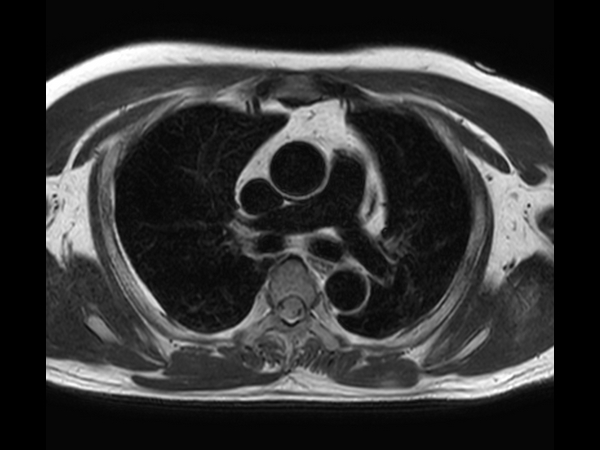

Axial T2w TSE - Black Blood